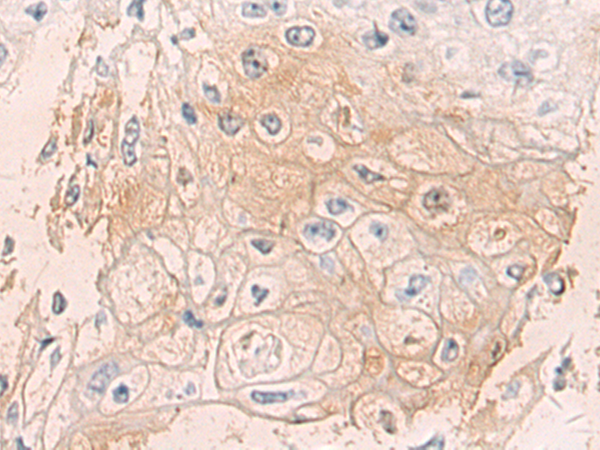

IHC positive control:

Human esophagus cancer

IHC Recommend dilution:

50-100